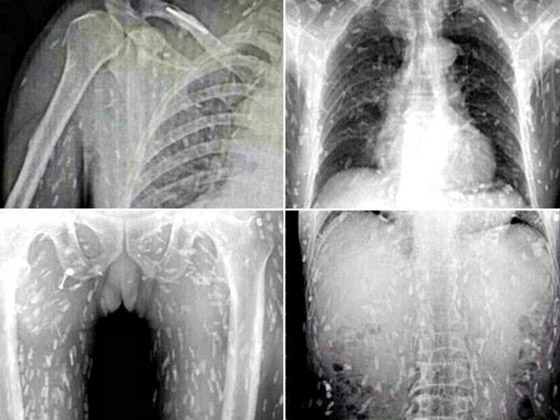

14- الورم الوحشي: يعد الورم الوحشي نوعا من الخلايا السرطانية التي تنمو بداخل جسم الإنسان. يعتبر هذا النوع من الأورام من أغرب الأنواع التي تم اكتشافها فهو لا يعد ورم عادي. تتكون خلايا هذا النوع من شعر، وأسنان، وعظام، وفي بعض الأحيان قد ينمو له أيدي أرجل وأعين!